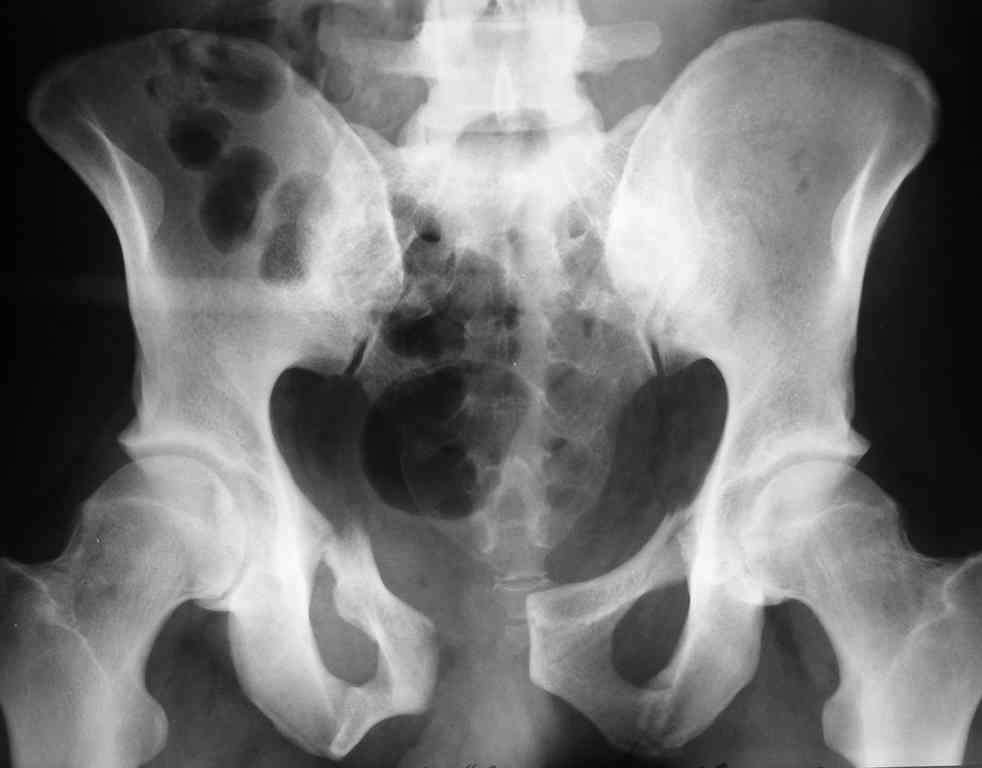

Уважаемые коллеги! опять вопрос по повреждению таза. Больной получил производственную травму 10 дней назад - удар балкой около 3 тонн в область верхней трети правого бедра и лона.

Был диагностирован перелом "типа бабочки" и повреждение уретры. Сделана цистостома. У насв отделении 3 дня. Имеется огромная флюктуирующая гематома с "галифе"-образной деформацией обеих бедер. Пнкционно эвакуировали в несколько приемов из подфасциальных полостей на бедрах около 3 литров геморрагического отделяемого с последующей эластической компрессией. При пункциях выявлено сообщение полостей на бедрах - видимо через поравннуюдиафрагму дна и полость таза - при удалении крови справа уменьшался объем левого бедра. Какой то активности проявялять покабоимся - аппаратная фиксация через отслоенные ткани представляется чреватой нагноением, открытая фиксация в условиях такой гематомы тоже не радует. Хотелось бы услышать ваше мнение

Типичная картина Morel-Lavallee повреждения.

18.12. - отдельное спасибо еще раз А.В.Рункову- больного оперировали (А.В.Рунков) - произведен остеосинтез аппаратом - фиксация за крылья, два стержня в лонные кости и репозиция (почти полная) снимки будут чуть позже.